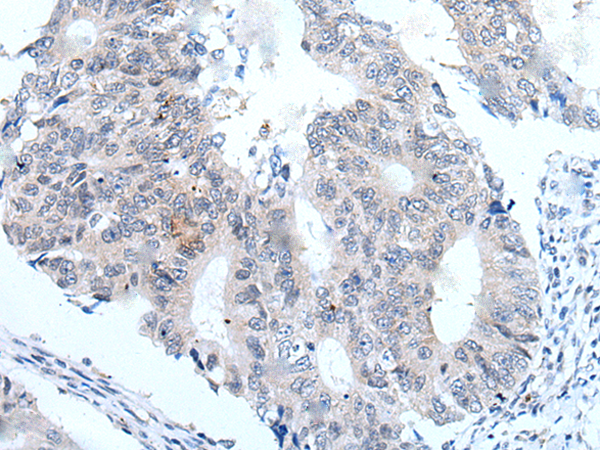

分类: 科研抗体货号: P12820别名: CENF; hcp-1; CILD31; PRO1779应用: IHC反应种属: Human

分类: 科研抗体货号: P12837别名: ZAP; ZC3H2; ARTD13; PARP13; FLB6421; ZC3HDC2应用: IHC反应种属: Human

分类: 科研抗体货号: P12836别名: C19orf7应用: IHC反应种属: Human, Mouse

分类: 科研抗体货号: P12818别名: ATG1; ATG1A; UNC51; hATG1; Unc51.1应用: IHC反应种属: Human

分类: 科研抗体货号: P12835别名: ZNF923应用: IHC反应种属: Human